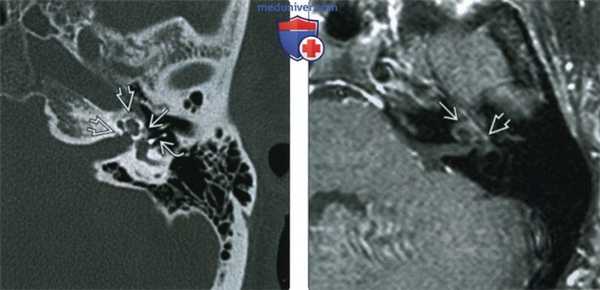

(Справа) При корональной КТ правой височной кости у пациента со смешанной тугоухостью визуализируется рентгенонегативное «гало» вокруг улитки, обусловленное кохлеарным отосклерозом. Обратите также внимание на сопутствующий фенестральный отосклероз.